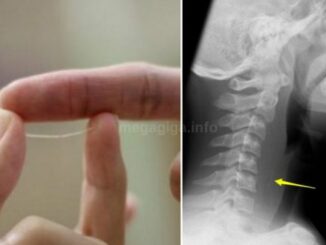

OVO SIGURNO NSITE ZNALI: Čaroban lijek za štitnjaču, srce, krv i kosti mi ga bacamo kao da je obično smeće!

Kalcij ima brojne važne funkcije u radu organizma. Osim što stvara koštanu masu i sprečava osteoporozu, kalcij normalizira rad živaca i mišića, regulira otkucaje srca, onemogućuje zgrušavanje krvi i potiče san. Također je važan za […]